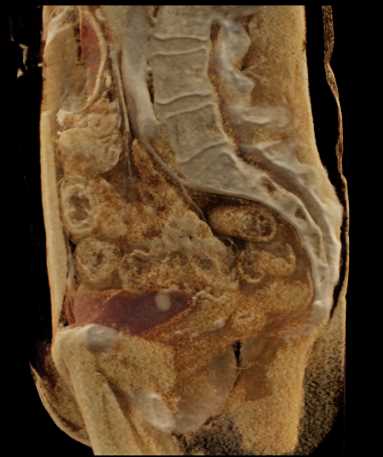

Urachal Carcinoma of the Bladder